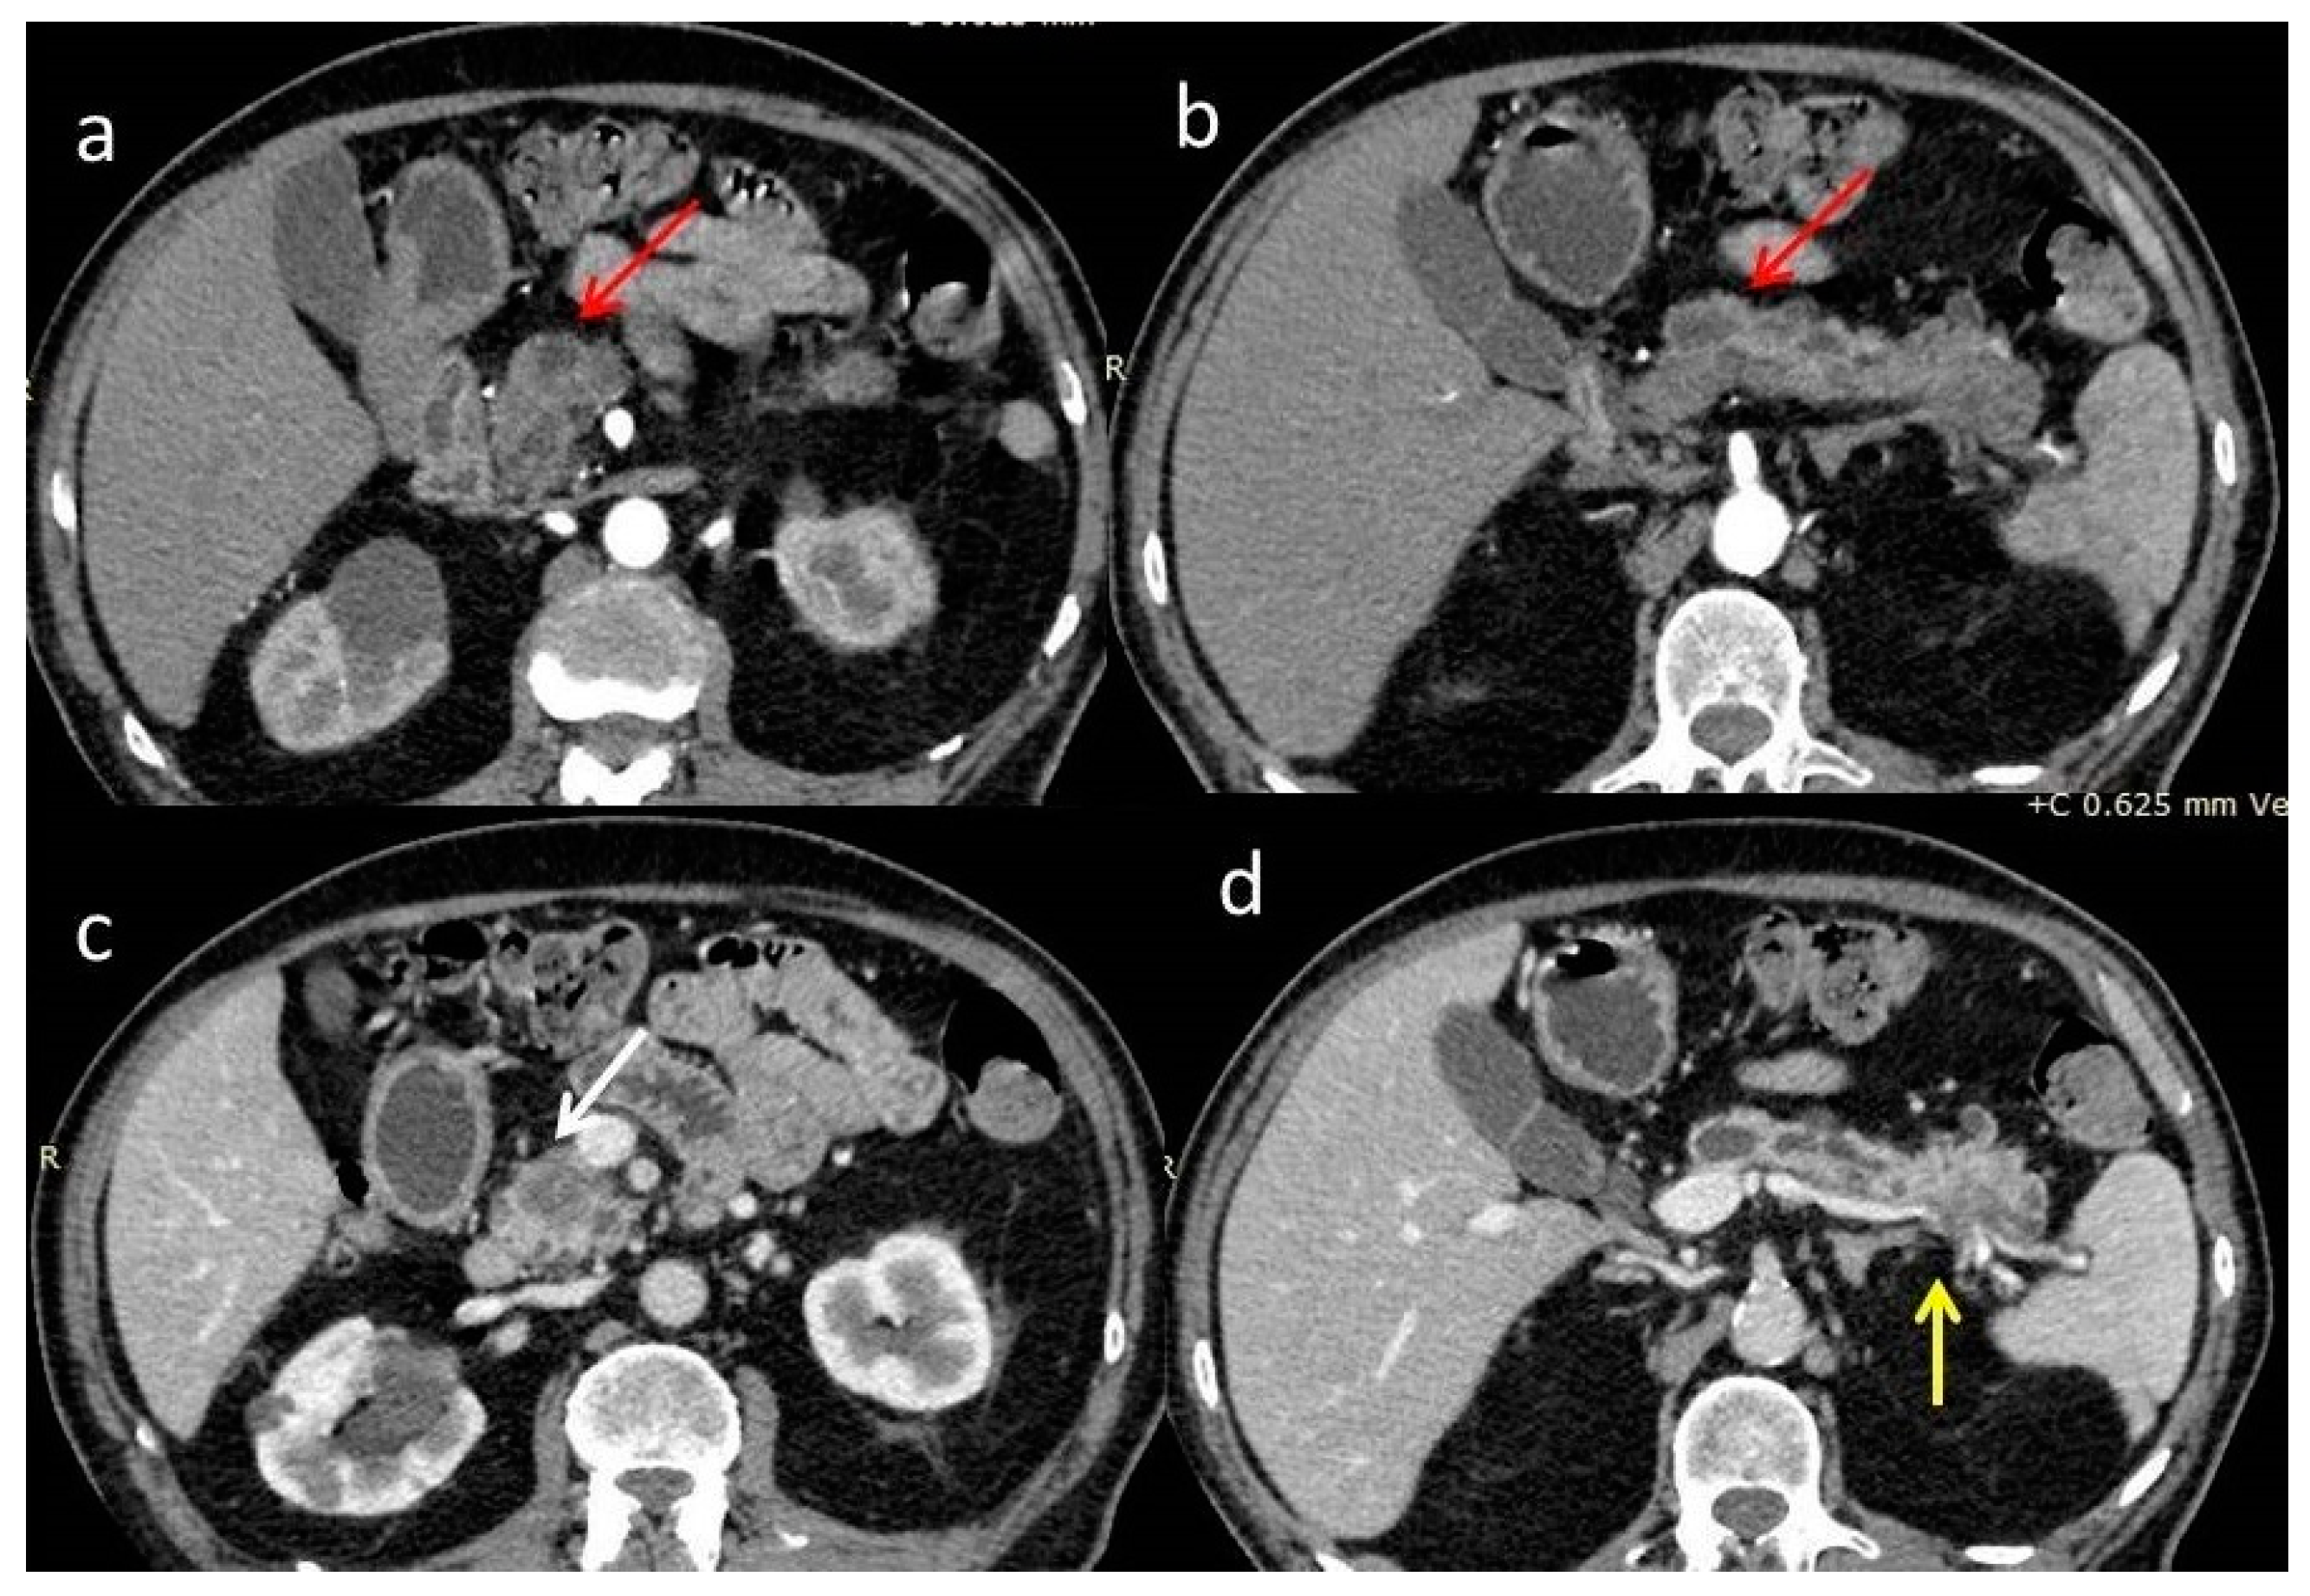

A new abdominal contrast-enhanced computed tomography scan (CECT), which confirmed the findings of the first one, revealed two ill-defined hypoenhancing lesions with a maximum diameter of 2.5 cm in the head and tail of the pancreas, obstruction and dilatation of the main pancreatic duct, and abutment of the superior mesenteric vein <90° by the head tumor, as well as infiltration of the wall of the splenic vein by the tail tumor. Hepatic and renal cysts and an enlarged mesenteric lymph node were also depicted. The main pancreatic duct and its branch ducts appeared anomalously dilated with multiple stenoses (Figure 2). These findings were considered suspicious for double pancreatic adenocarcinoma in the setting of chronic pancreatitis or intraductal papillary mucinous neoplasia (IPMN).

Figure 2.

(a,b) arterial phase and (c,d) venous phase of a contrast-enhanced computed tomography scan (CECT). Poorly enhanced masses at the head and tail (red arrows) of the pancreas with surrounding fat stranding. The mass at the head of the pancreas occludes the pancreatic duct, causing peripheral dilatation (white arrow). Limited contact with the posterior surface of the superior mesenteric vein <90°. The mass of the tail invades the splenic vein (yellow arrow). Abnormal dilatation of the main pancreatic duct with strictures is demonstrated with multiple collateral cystic lesions.